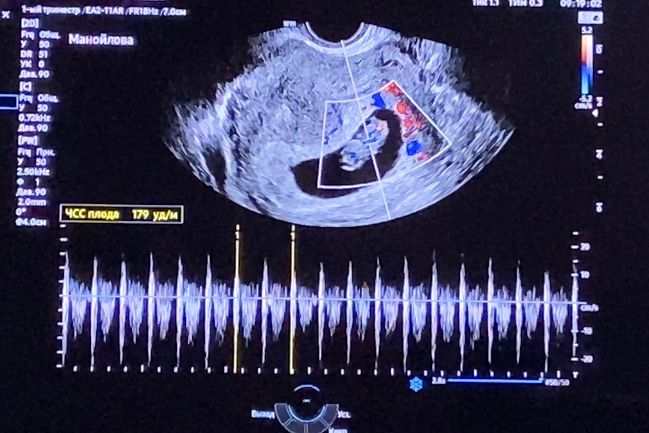

Узи в 9 недель и 2 дня.

Как я дождалась конца декабря до сих пор поражаюсь, но мой токсикоз заполнил всё пространство и *спасибо* ему, что дни пролетели так быстро. Моё второе узи, сейчас срок по месячным 9.2 недель первое было 1.12 на сроке 5.6.

итак, услышала сердцебиение 💗

чсс 179

Внутренний диаметр пя 33.2 на 8.5 недель

ктр 23.9 на 8,6 недель

жм - 4 мм

по узи получается отставание на 3-4 дня, как и было на 1 узи, думаю ничего страшного..